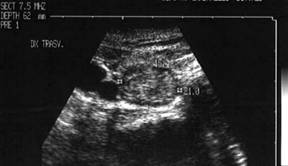

Nodul hipoecogen, neomoge, cu contur net, de 15x21x27 mma (4 cc) in lobul drept.

Examen citologic prin citoaspirate: nodul hiperplazic.